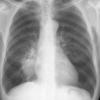

Case 2  Lingular pneum Lat

Date: 04/17/2005

Views: 7033